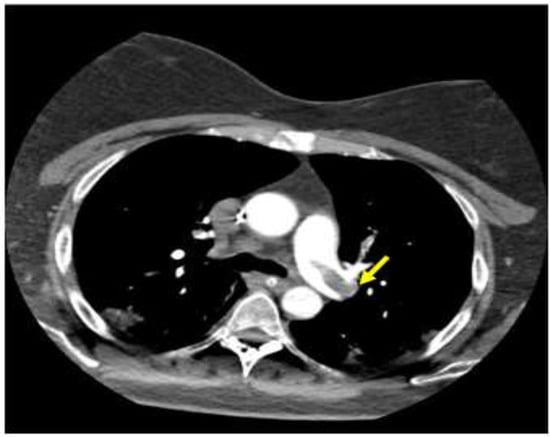

- Del Castillo-García, S.; Minguito-Carazo, C.; Echarte, J.C.; Rodríguez-Santamarta, M.; González, T.B.; Terroba Seara, S.; MartìnezGonzález, L.; Fernández-Vázquez, F. A case report of arterial and venous thromboembolism in a patient with severe COVID-19 pneumonia. Eur Heart J Case Rep. 2020, 17, 1–6. [Google Scholar]